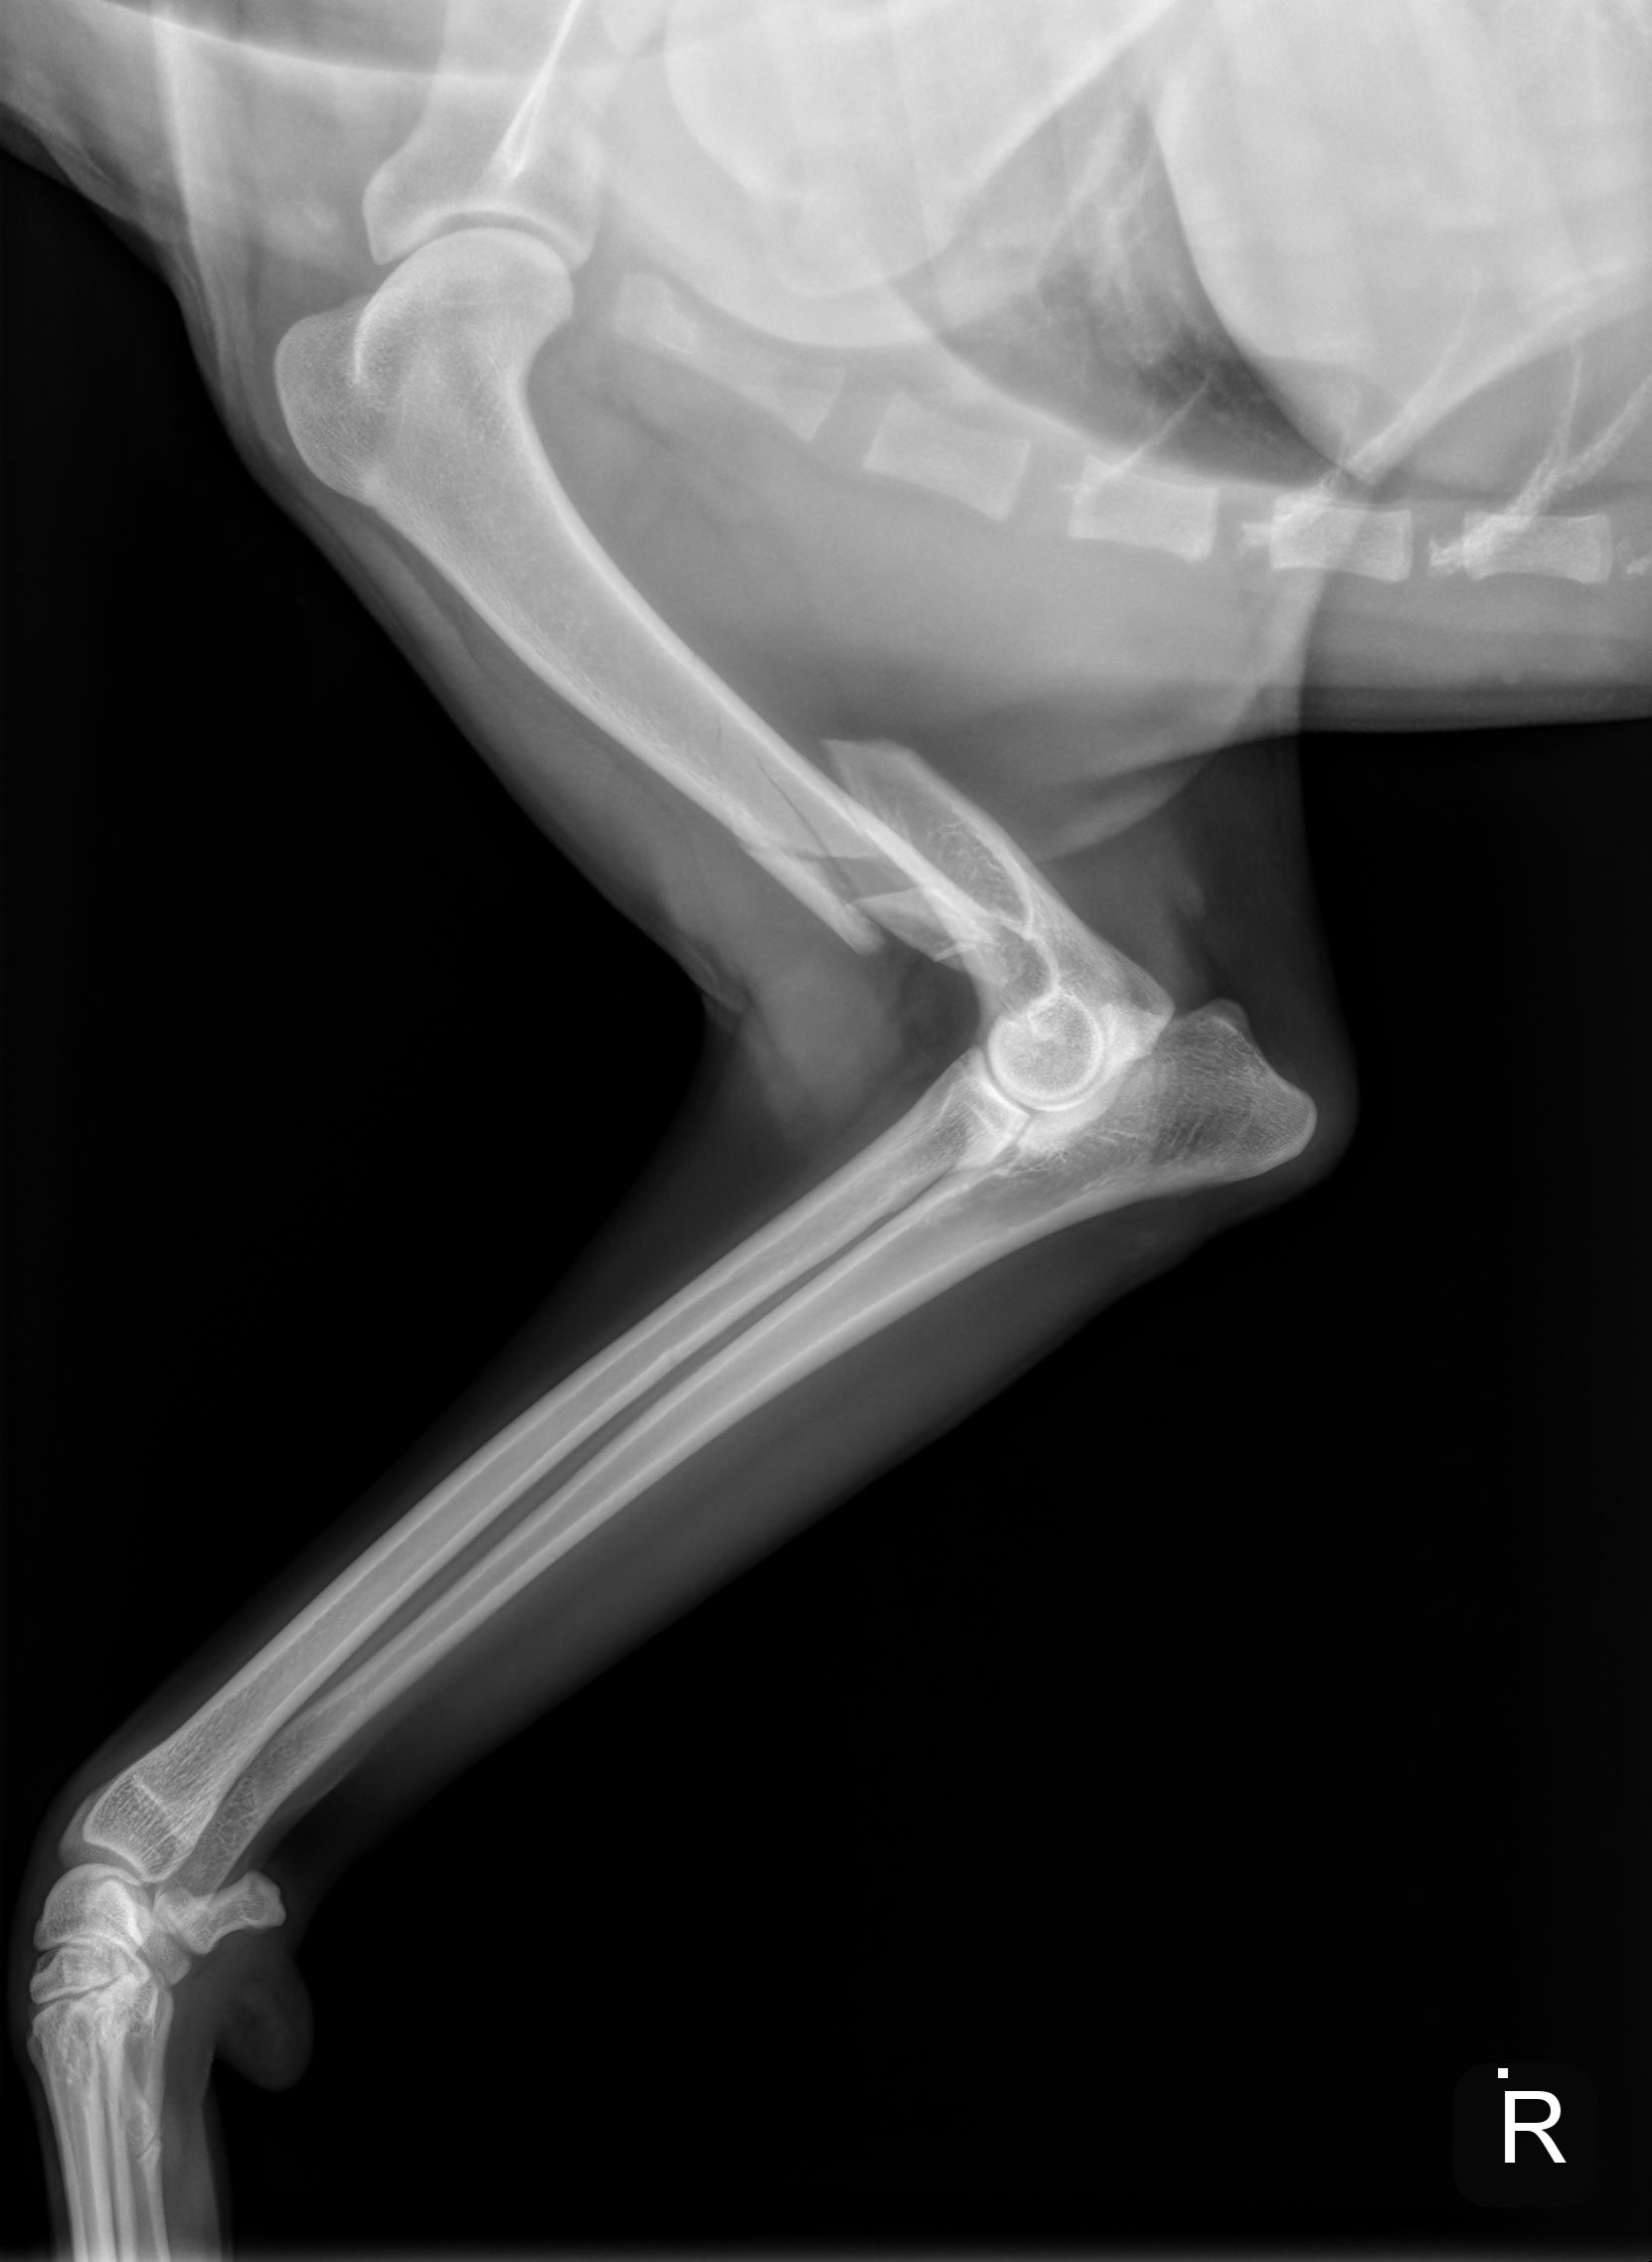

River is a sweet, gentle 1 1/2 year old golden, who had a tragic fall down a flight of stairs and fractured his humerus bone. Due to financial hardship and the physical challenges of navigating multiple flights of stairs, River’s family made the heartbreaking decision to surrender him to GRR so he could receive the care he desperately needed.

This type of injury is incredibly painful and requires specialized surgery to repair. Without it, River’s chances of ever walking, playing, or living a pain-free life are at risk. Watching him struggle to stand and looking into his eyes as he winces in pain is heartbreaking.

On Tuesday (10/30/2025) afternoon, his leg was surgically repaired using plates, screws & pins.  We are hoping his will be fully recovered in 8 weeks.